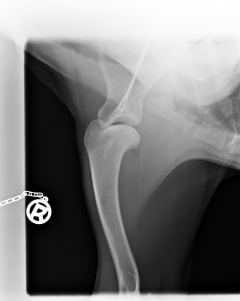

Bayou ist HD frei, ED frei und OCD frei.Beste Vorraussetzung für ein Deckrüde.

HD                                                           ED-Rechts                                         ED-Links                                                 OCD-rechts                                            OCD-links